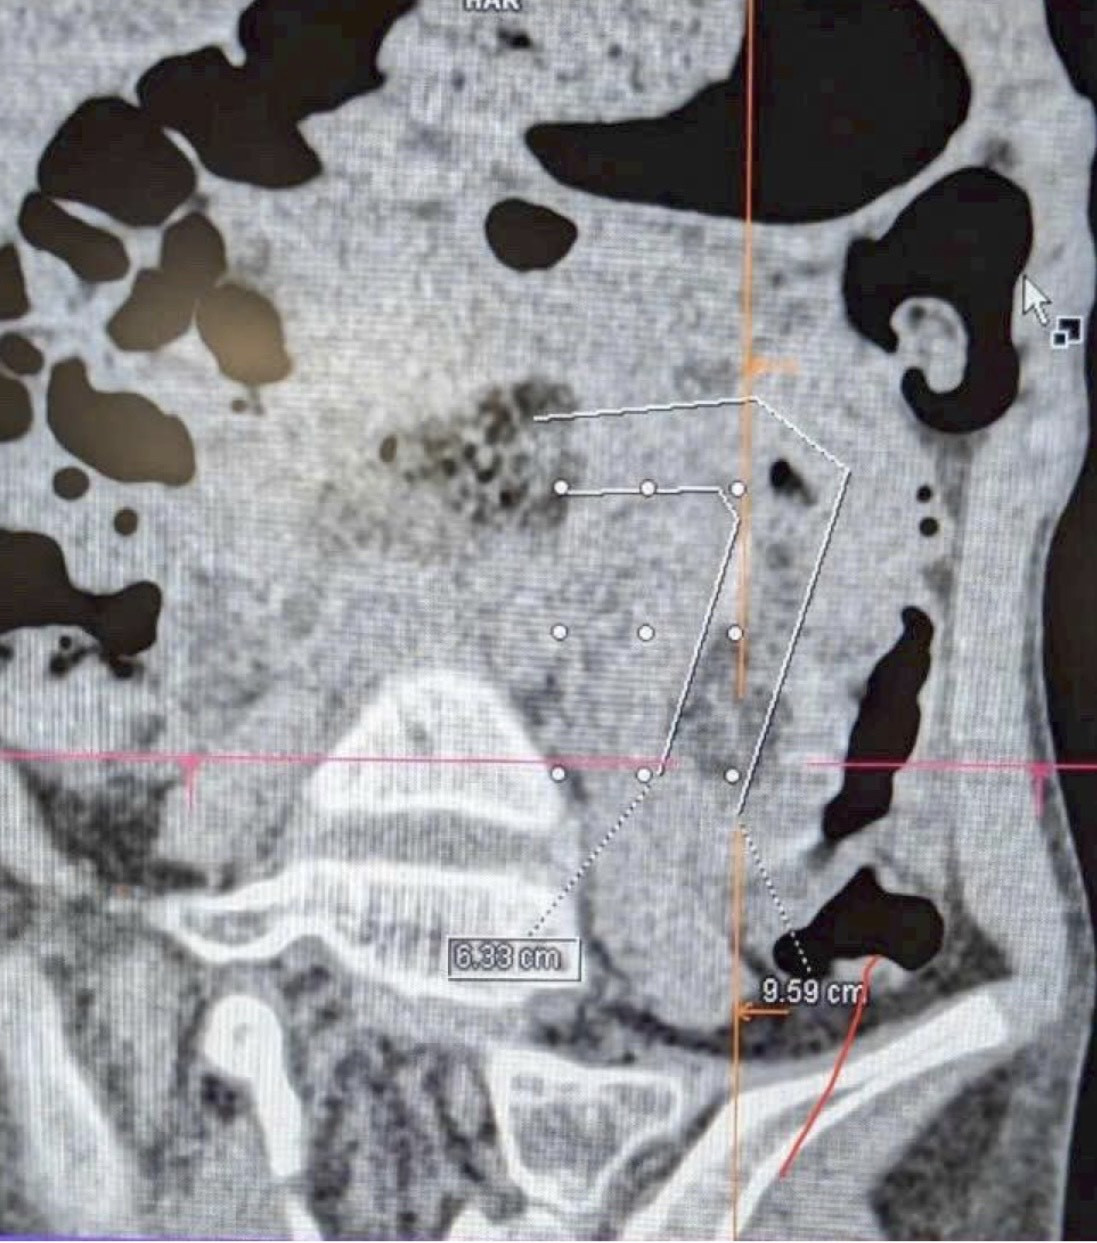

Bé H. (9 tuổi, TP.HCM) được gia đình đưa đến Bệnh viện FV trong tình trạng đau bụng nhiều ngày, nôn ói liên tục, người gầy và da xanh xao. Những biểu hiện ban đầu dễ khiến mọi người nghĩ đến rối loạn tiêu hóa, nhưng kết quả khám chuyên sâu và hội chẩn giữa các bác sĩ Ngoại tổng quát - Tiêu hóa - Chẩn đoán hình ảnh cho thấy nguyên nhân nghiêm trọng hơn nhiều: trong bụng bé có một búi tóc dài gần 1m, bện chặt như dây thừng, kéo từ dạ dày xuống ruột non và gây tắc hoàn toàn.

Các bác sĩ FV đánh giá đây là ca bệnh hiếm gặp và phức tạp do búi tóc lớn, cuộn chặt và kéo dài qua nhiều đoạn ruột. Nếu xử lý không đúng cách, nguy cơ hoại tử và đe dọa tính mạng bệnh nhi cao.

Sau hội chẩn, các bác sĩ quyết định kết hợp nội soi tiêu hóa từ trên và phẫu thuật nội soi ổ bụng từ dưới nhằm hạn chế tối đa xâm lấn. Phẫu thuật nội soi ổ bụng cho phép các bác sĩ tiếp cận phần ruột bị tắc, trong khi nội soi tiêu hóa hỗ trợ xác định vị trí và thao tác gỡ từ phía dạ dày. Sự kết hợp hai kỹ thuật xâm lấn tối thiểu này giúp bệnh nhi không phải trải qua ca mổ hở và nhờ vậy phục hồi nhanh sau điều trị.

Sự phối hợp nhịp nhàng giữa hai ê-kíp giúp hạn chế tối đa nguy cơ tổn thương ruột. Sau khoảng 3 giờ, búi tóc được lấy ra an toàn, giải quyết hoàn toàn tình trạng tắc ruột.